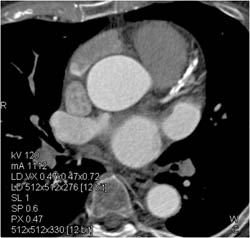

Myocardial Bridging of LAD